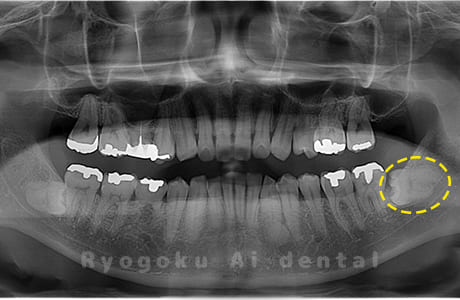

Case09

-

- 原因

- 下顎左の水平埋伏智歯

- 治療内容

- 下顎左の水平埋伏智歯を抜歯したケースです。

<リスク・副作用>

手術後は痛み、腫れ、痺れなどの副作用が生じる場合があります。